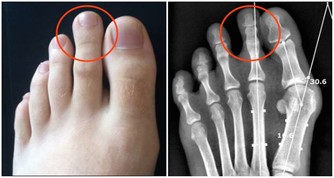

1.如果感覺到了肩周炎的典型症狀:肩膀疼痛、關節活動受限,

但同時還有低熱、盜汗、乏力、臉色蒼白、消瘦等症狀,要提防肩關節結核。

2.肩部腫瘤也會引起肩痛、肩臂活動功能障礙,

如果覺得肩痛逐漸加重、疼痛部位擴大,可別再「惦記」肩周炎,一定要做進一步檢查。